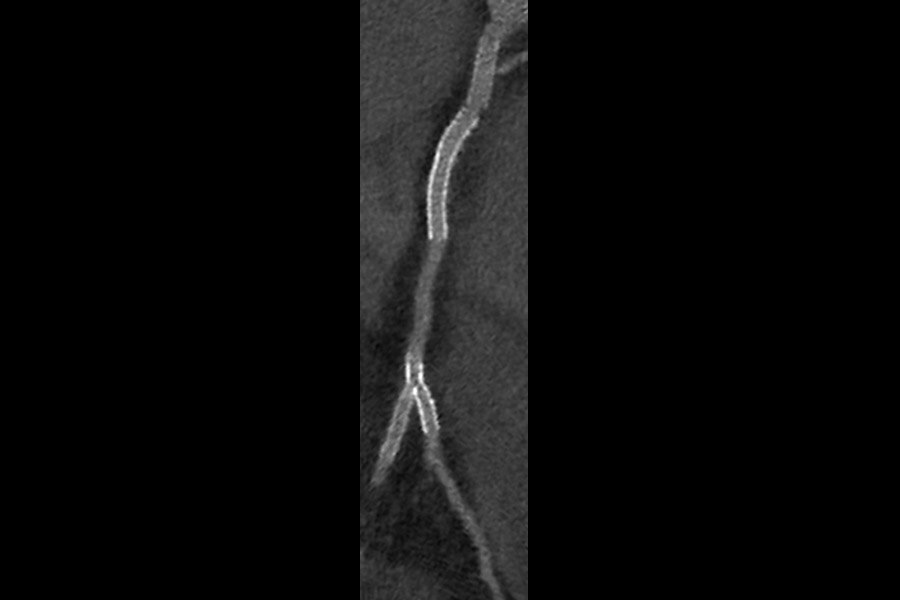

Visualization of the lumen of stents on 53-year-old male, 51 BPM, BMI 31